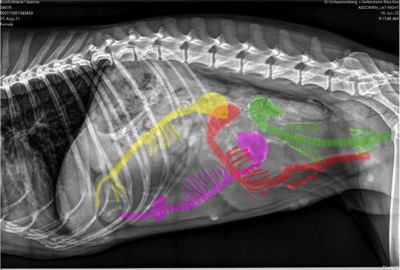

Unsere bezaubernde Jeannie „Tova‘s Riesling Surprise in Germany“ wurde Ende April von unserem charmanten Mio „Golden Nugget's Achilles“ gedeckt.

Wir erhoffen uns von dieser Verpaarung von zwei F3 Windsprites eine Erhöhung der genetischen Diversität mit den damit verbundenen positiven Auswirkungen auf die langfristige Gesundheit der Rasse. Apropos Gesundheit: Jeannie und Mio sind bereits 3,5 und 5,5 Jahre alt. Bis zur Zulassung der F3 Silken Windsprites hat es ja bekanntlich einige Jahre gedauert. Positiv daran ist, dass wir wissen, dass beide Hunde eine phantastische Konstitution und Gesundheit haben. Beide sind körperlich total fit und wirklich robust und unempfindlich – eigentlich waren sie noch nie richtig krank und vertragen jedes Futter.